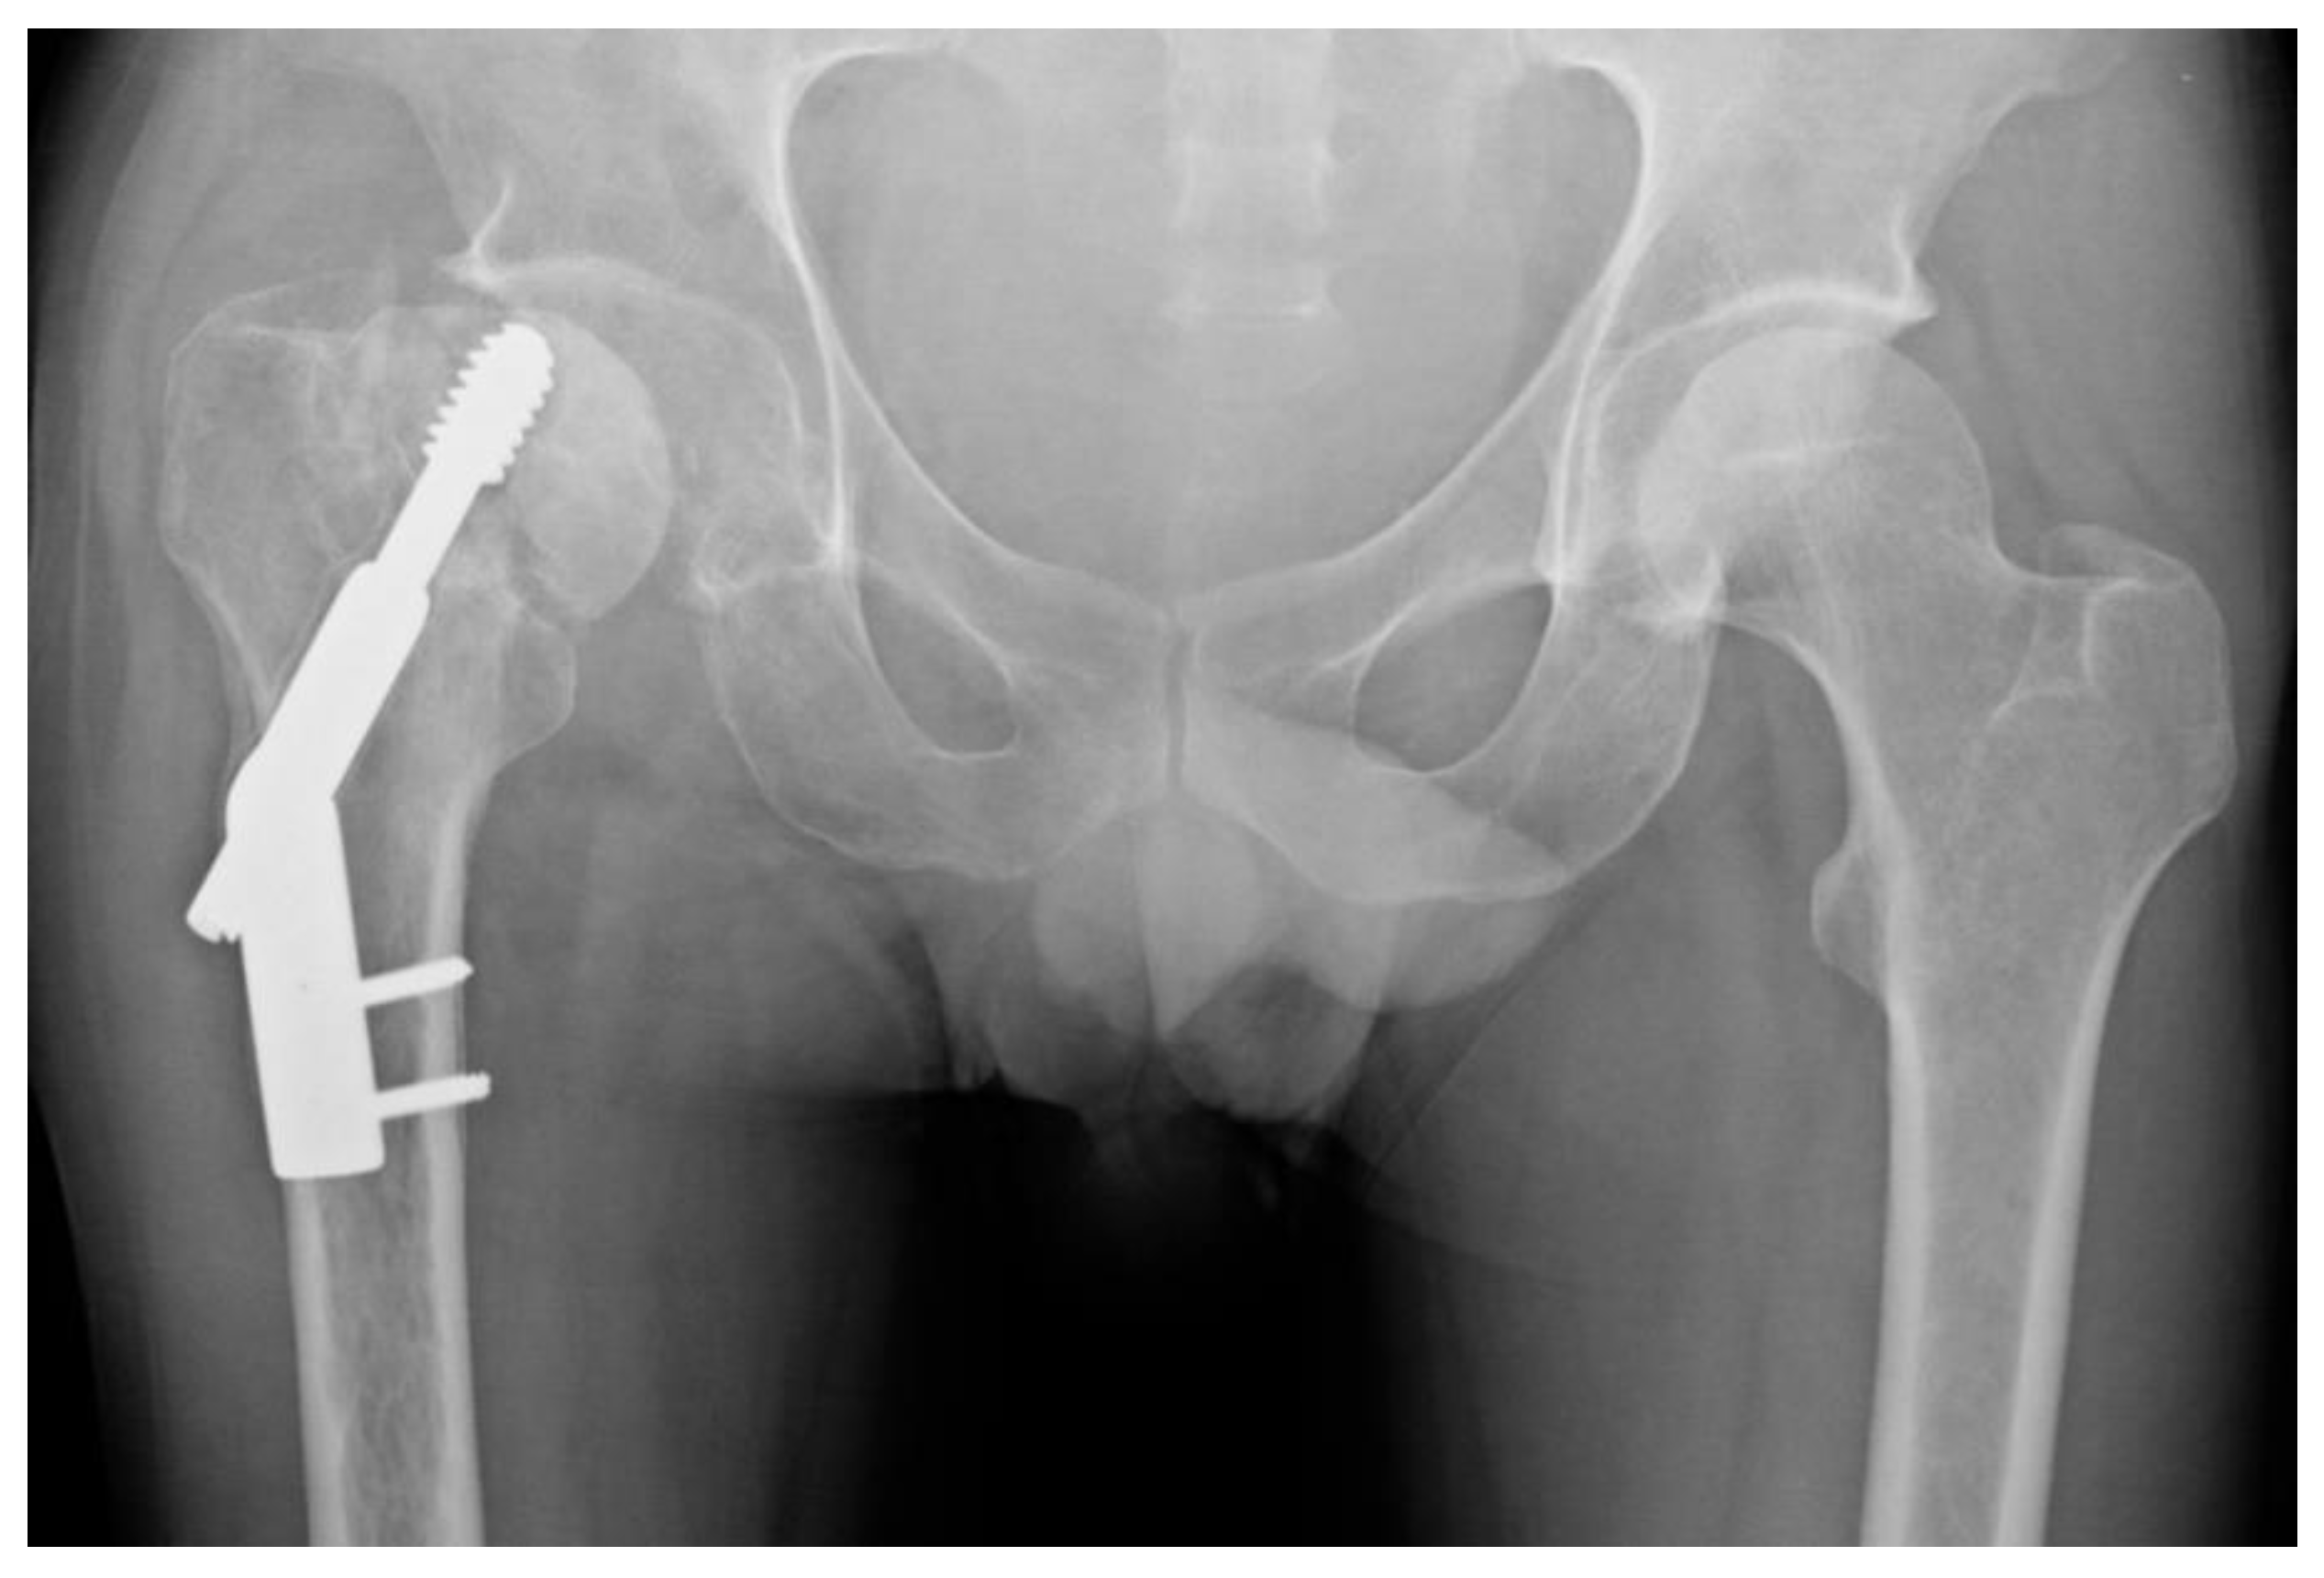

A Comparison of Dynamic Hip Screw and Two Cannulated Screws in the Treatment of Undisplaced Intracapsular Neck Fractures—Two-Year Follow-Up of 453 Patients

Widhalm, H.K.; Arnhold, R.; Beiglböck, H.; Munteanu, A.; Lang, N.W.; Hajdu, S. A Comparison of Dynamic Hip Screw and Two Cannulated Screws in the Treatment of Undisplaced Intracapsular Neck Fractures—Two-Year Follow-Up of 453 Patients. J. Clin. Med. 2019, 8, 1670. https://doi.org/10.3390/jcm8101670